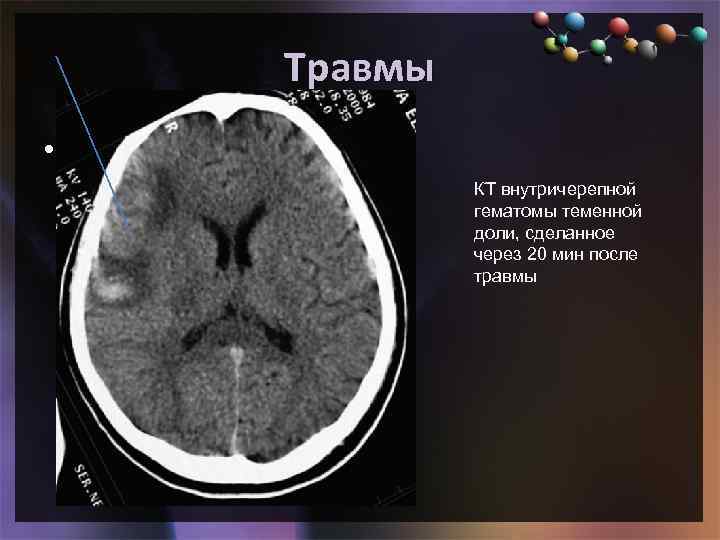

Травмы • Подзаголовок слайда КТ внутричерепной гематомы теменной доли, сделанное через 20 мин после травмы

Травмы • Подзаголовок слайда КТ внутричерепной гематомы теменной доли, сделанное через 20 мин после травмы